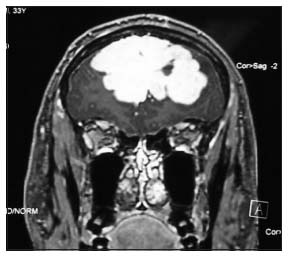

| Figure 4 Magnetic resonance imaging of pineal tumor